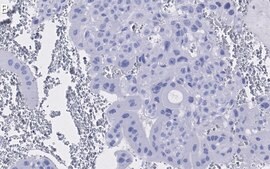

Immunohistochemistry (Paraffin) Analysis: A 1:100 dilution from a representative lot detected PPAR in human placenta tissue sections.